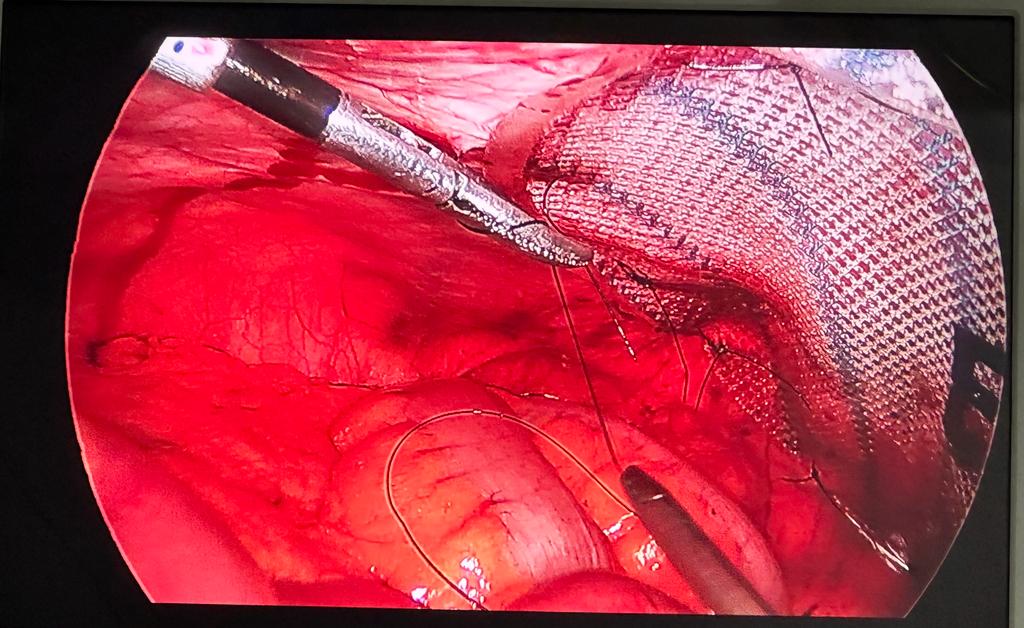

Laparoscopic Hernia repair